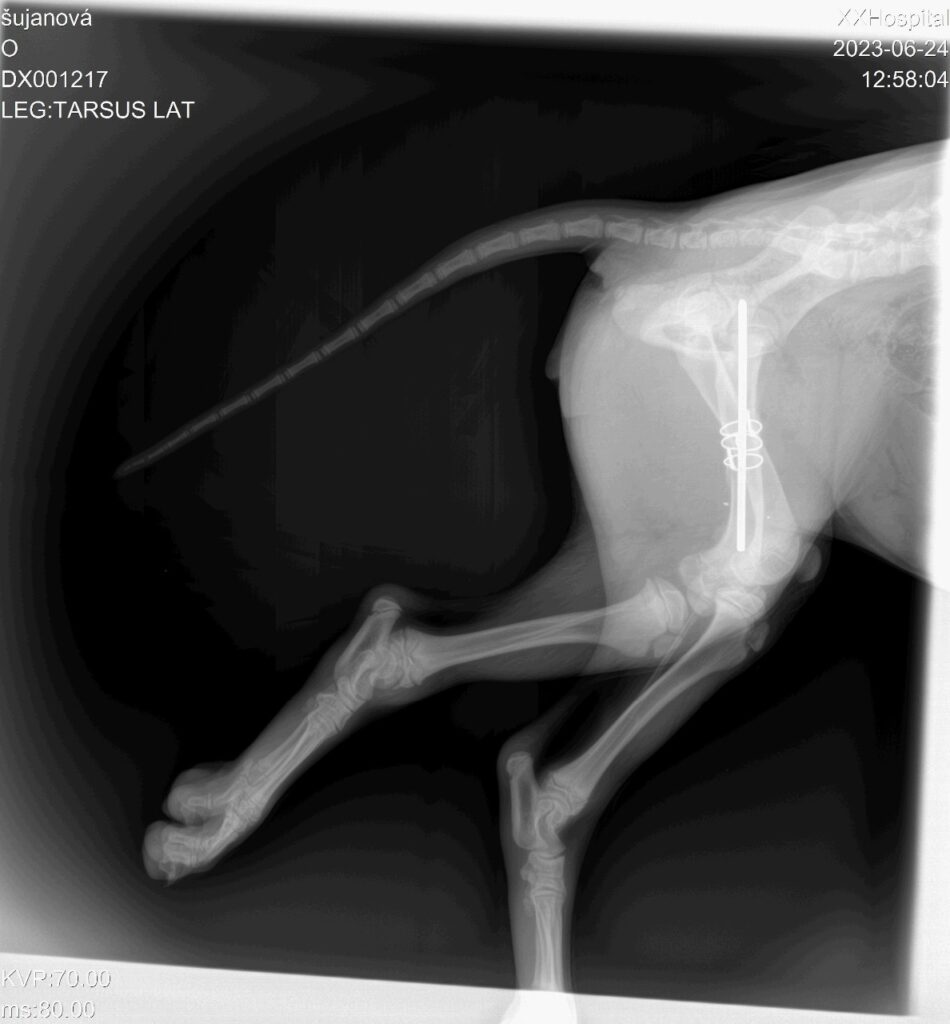

Z praxe

Reálné zákroky a ošetření z naší ordinace.